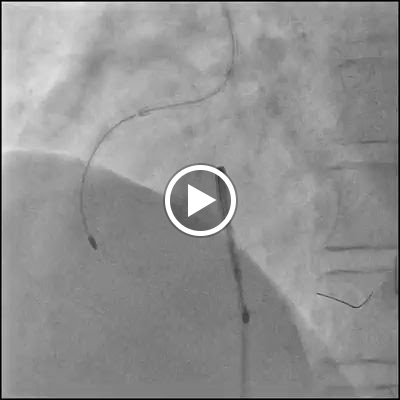

Dr. Kush Kumar Bhagat is an Interventional cardiologist and Electrophysiologist presently working at Eternal Hospital, Jaipur as Associate Director, Interventional Cardiology and Electrophysiology. He has been successfully performing all routine and complex coronary and peripheral heart disease interventional procedures such as coronary and peripheral angiograms, multivessel and primary PCI, IVUS imaging and FFR. He has special expertise in the management of rhythm related issues of the Heart. He has knowledge of performing interventional electrophysiology procedures for management of heart rhythm disorders which includes Electrophysiological studies and Radiofrequency ablations including RF ablations under 3D mapping (both CARTO and NAVX)